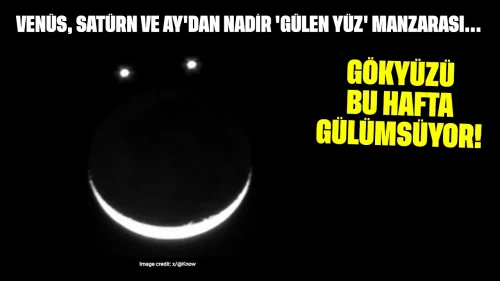

- Göğüs Ağrısı: Kalp krizinin en bilinen belirtisidir. Sıkışma, baskı veya ağrı hissi olarak tanımlanabilir.

- Nefes Darlığı: Efor sırasında veya dinlenirken ortaya çıkabilir. Kalbin yeterince kan pompalayamaması durumunda oluşur.

- Çarpıntı: Kalp atışlarının hızlı, düzensiz veya güçlü hissedilmesi. Anksiyete veya aşırı kafein tüketiminden kaynaklanabileceği gibi ciddi bir sorunun belirtisi de olabilir.

- Baş Dönmesi ve Bayılma: Bu belirtiler, beyin kan akışının azalmasıyla ortaya çıkabilir ve acil müdahale gerektirir.

- Şişlik: Ayaklarda, bacaklarda veya karında sıvı birikmesi, kalp yetmezliğinin bir işareti olabilir.

- Yorgunluk: Aşırı yorgunluk, kalp hastalığının gizli bir belirtisi olarak kendini gösterebilir.

- Terleme: Normalden fazla terleme, özellikle dinlenme halinde meydana geliyorsa dikkat edilmelidir.

- Mide Bulantısı ve Kusma: Bu belirtiler, kalp problemlerinin belirtisi olarak ortaya çıkabilir.

- Çene veya Sırt Ağrısı: Kalp krizi sırasında ağrı genellikle çene veya sırta yayılabilir.

- Egzersiz Toleransında Azalma: Normal aktiviteleri yaparken yorgunluk hissi, kalp sağlığı açısından risk işareti olabilir.

- Hızlı veya Düzensiz Nabız: Bu durum, kalp ritminde anormalliklerin belirtisi olabilir.